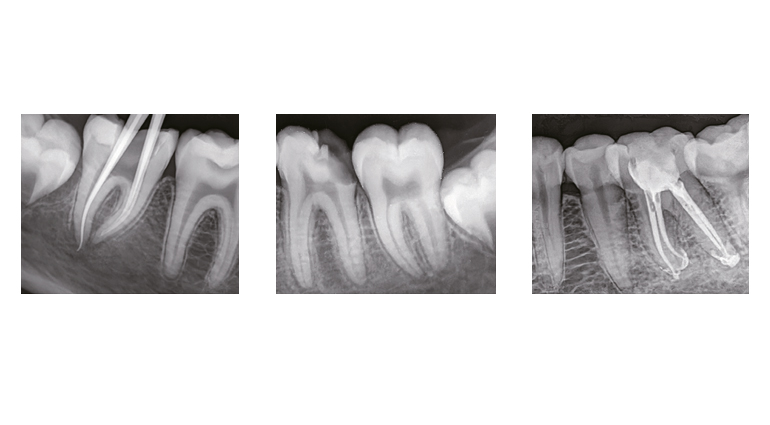

Grazie all’imaging diretto, evita la dispersione luminosa tipica dei sistemi indiretti, garantendo immagini cliniche stabili, nitide e ad altissima qualità.

La sua ampia gamma dinamica elimina la necessità di continue regolazioni dei tempi di esposizione, riducendo i tempi operativi e semplificando il flusso di lavoro.

Inoltre, è possibile modificare contrasto e luminosità in base alle diverse esigenze cliniche, per una diagnosi più precisa e personalizzata.

Grazie a questa innovazione, il sensore offre immagini nitide e prive di sfocature, garantendo una diagnosi più precisa e un’esperienza di lavoro più efficiente.